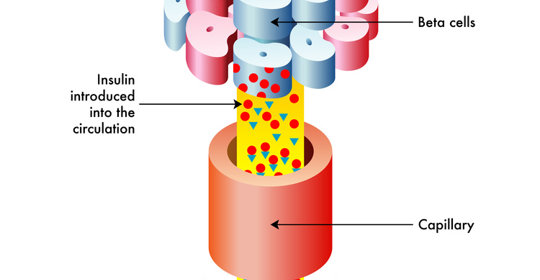

甲狀腺機能亢進:飲食、治療、預防、結節、頭痛